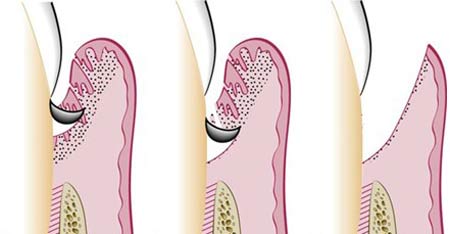

کورتاژ لثه (خراشیدن لثه)

این تکنیک جراحی لثه شامل خراشیدن بافت ناسالم از بخش عفونت کرده لثه و در نهایت التیام لثه سالم باقی مانده است.